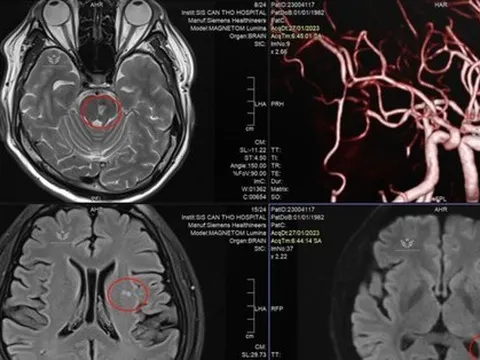

Doanh nhân trẻ đột quỵ vì thường xuyên tiếp đối tác bằng rượu bia

Nam doanh nhân 41 tuổi, đến bệnh viện trong tình trạng tê yếu nửa người do nhồi máu não. Khai thác bệnh sử của bác sĩ từ phía người bệnh ghi nhận, trước đó doanh nhân trẻ thường xuyên tiếp đối tác bằng rượu bia.